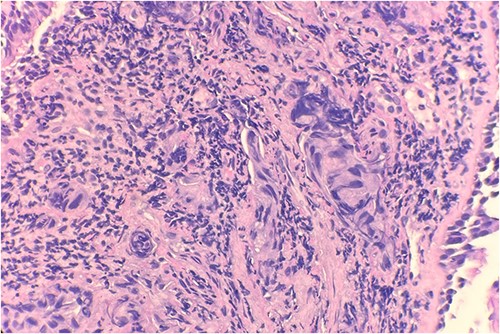

Pathology evaluation from the right middle lobe biopsy showed few clusters of malignant cells, consistent with ADC (Fig. 1). Immunohistochemical staining showed tumor cells were positive for AE1/3, Napsin A and TTF1 (Fig. 2), with ⁓60% Ki-67 positivity. Tumor cells were also negative for CK7 (Fig. 3), p40, p63, CK20 and CK5/6. The overall tumor morphology features and immunoprofile favored moderately differentiated ADC of the lung. However, other primary sites could not be ruled out.

Tumor cells are negative for CK7 by immunohistochemical stain IHC 20×.